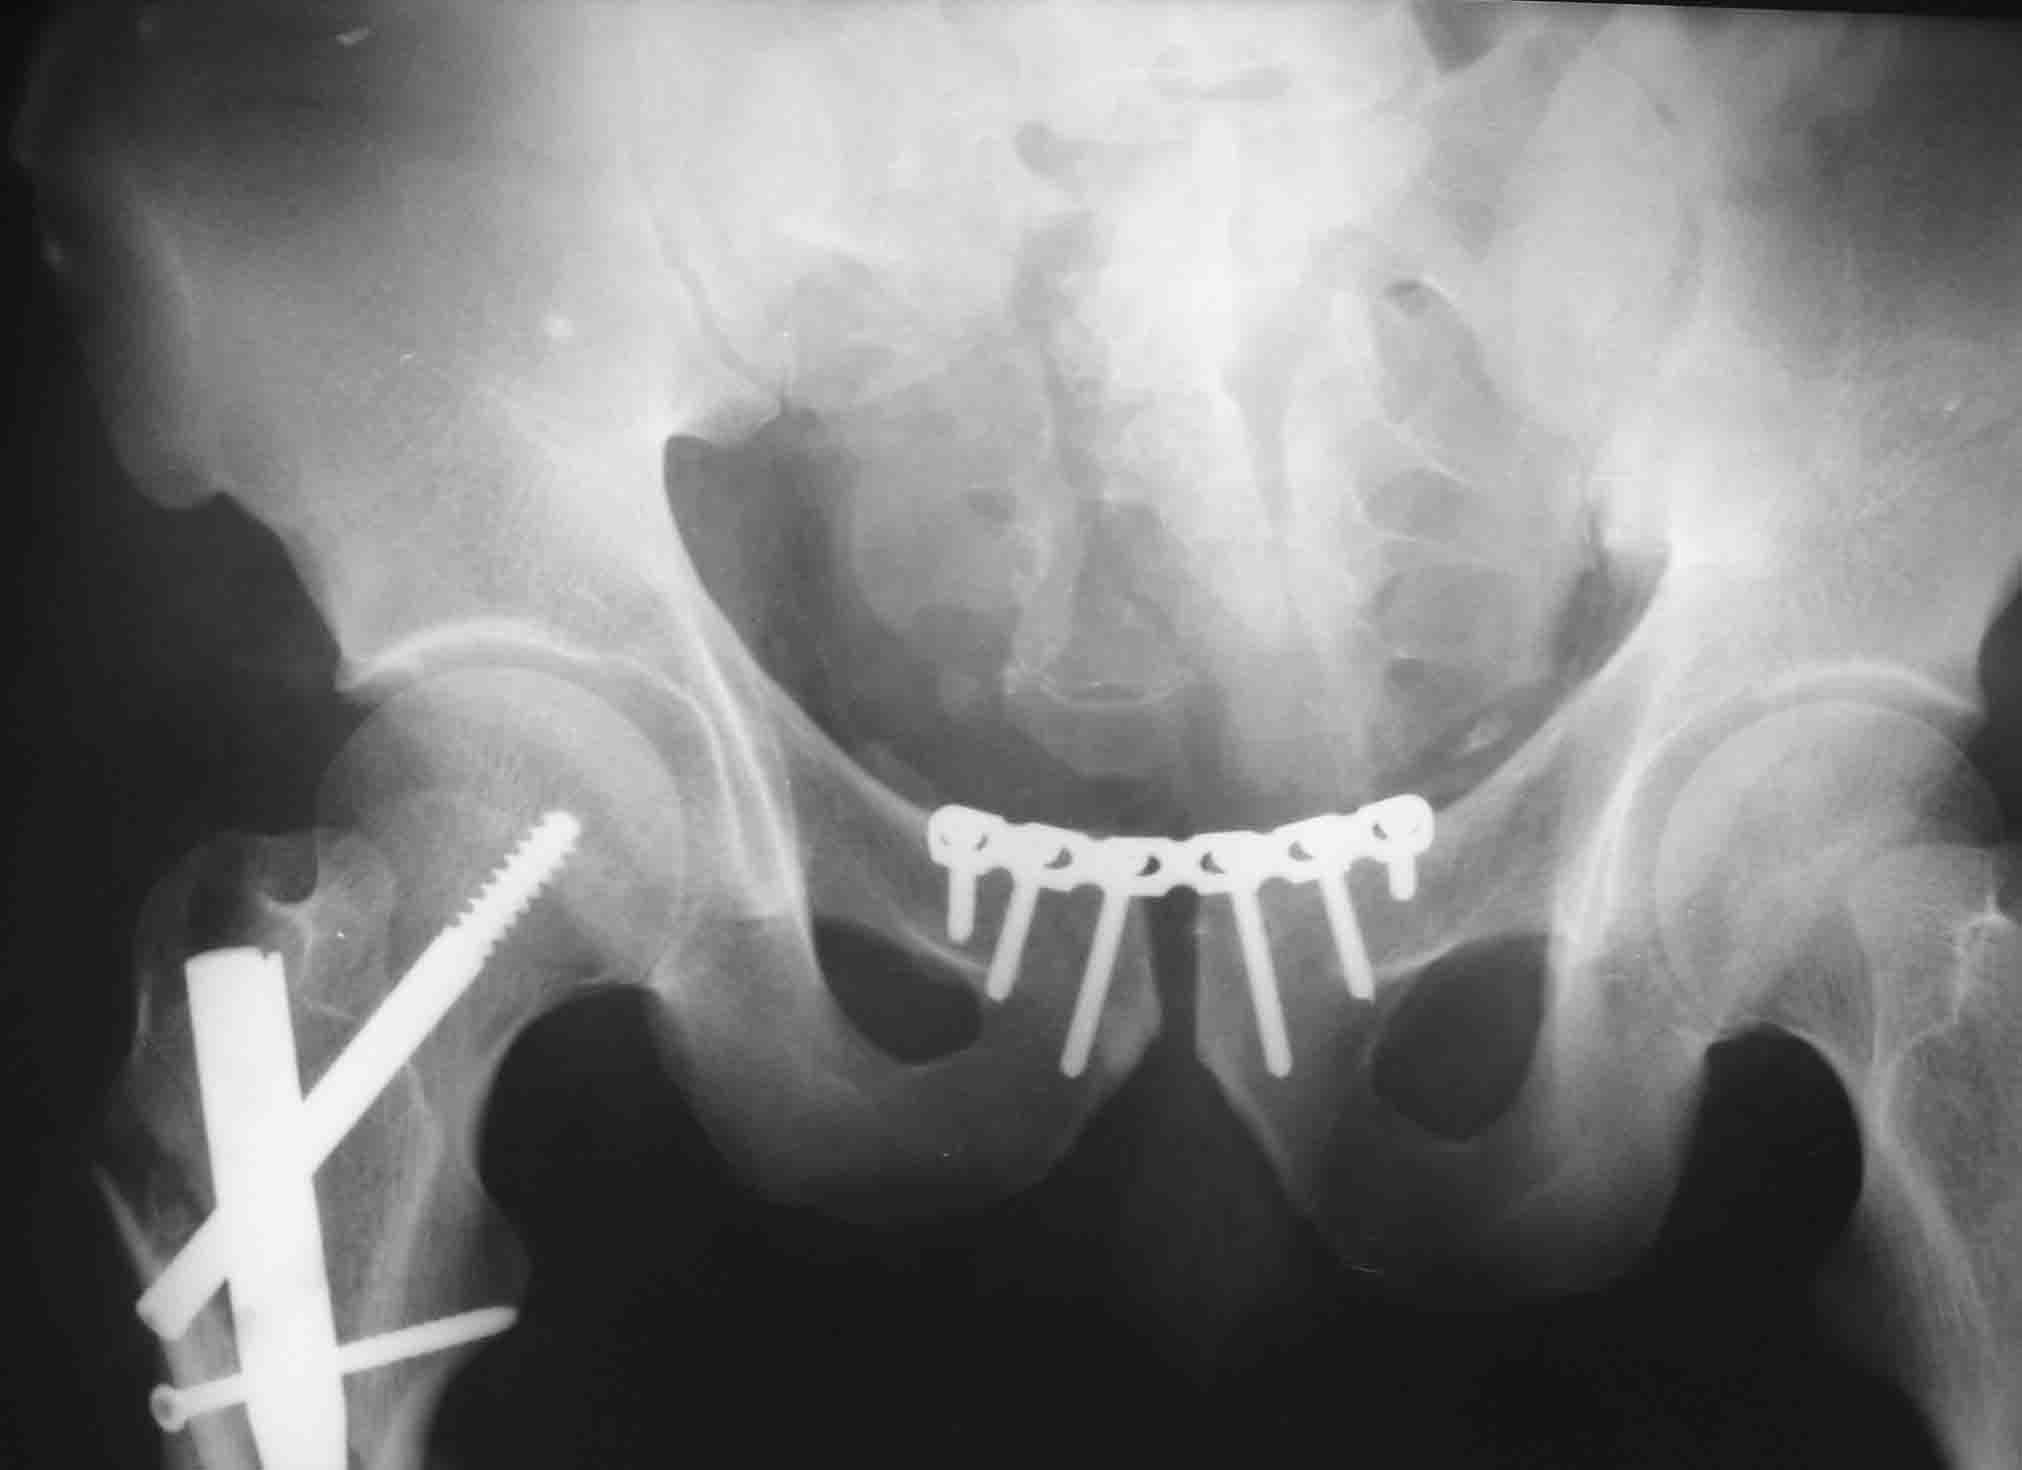

Имя     : 2.jpg

Тип     : application/octet-stream

Размер  : 36697 байтов

Описание: отсутствует

Url     : http://weborto.net:8080/pipermail/ortho/attachments/20071122/26706052/attachment-0006.obj